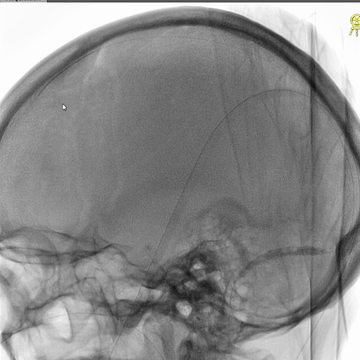

右侧颈动脉造影(正侧位):上矢状窦和直窦未见显影;右侧横窦和乙状窦少许显影。

左侧颈动脉造影(正侧位):上矢状窦前部少许显影,直窦未见显影,左侧横窦和乙状窦显影纤细。